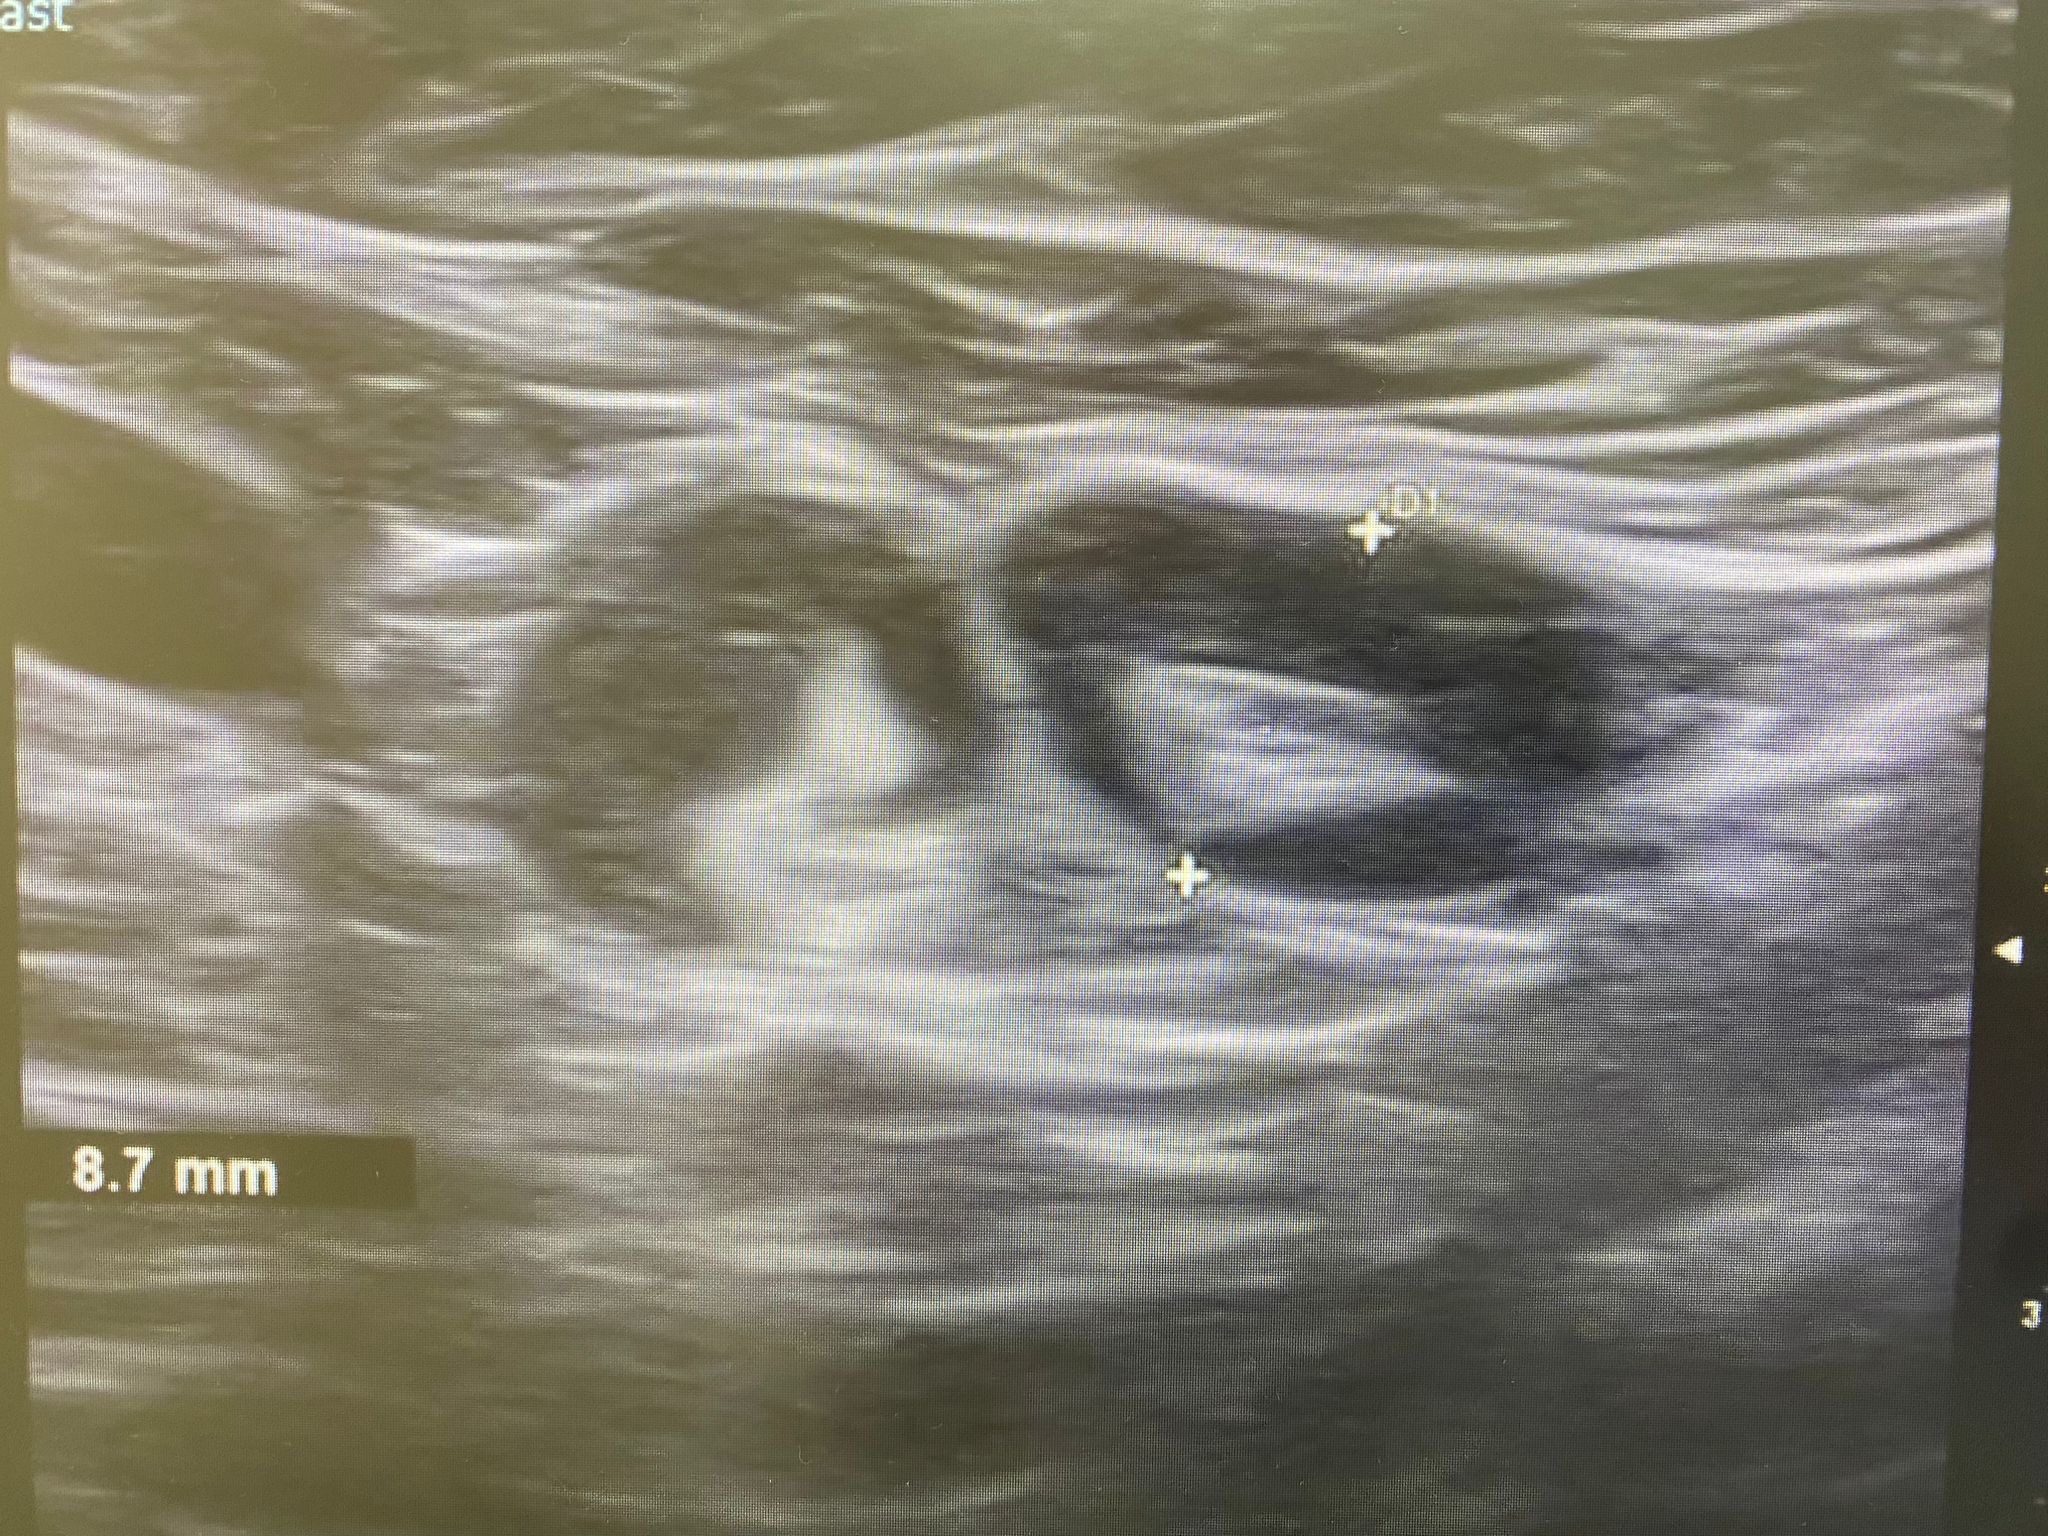

Ecografía: Valoración de adenopatías para acercamiento diagnóstico (típicas/atípicas).

Adenopatías patológicas, algunas redondeadas, con eje anteroposterior > 1 cm, parénquima homogéneo, cortical engrosada aunque con hilio respetado.

Ecografía mamas: quistes y nódulos hipoecogénicos bilaterales.

Ecografía axilar: múltiples adenopatías con eje corto > 2 cm y cortical engrosada.